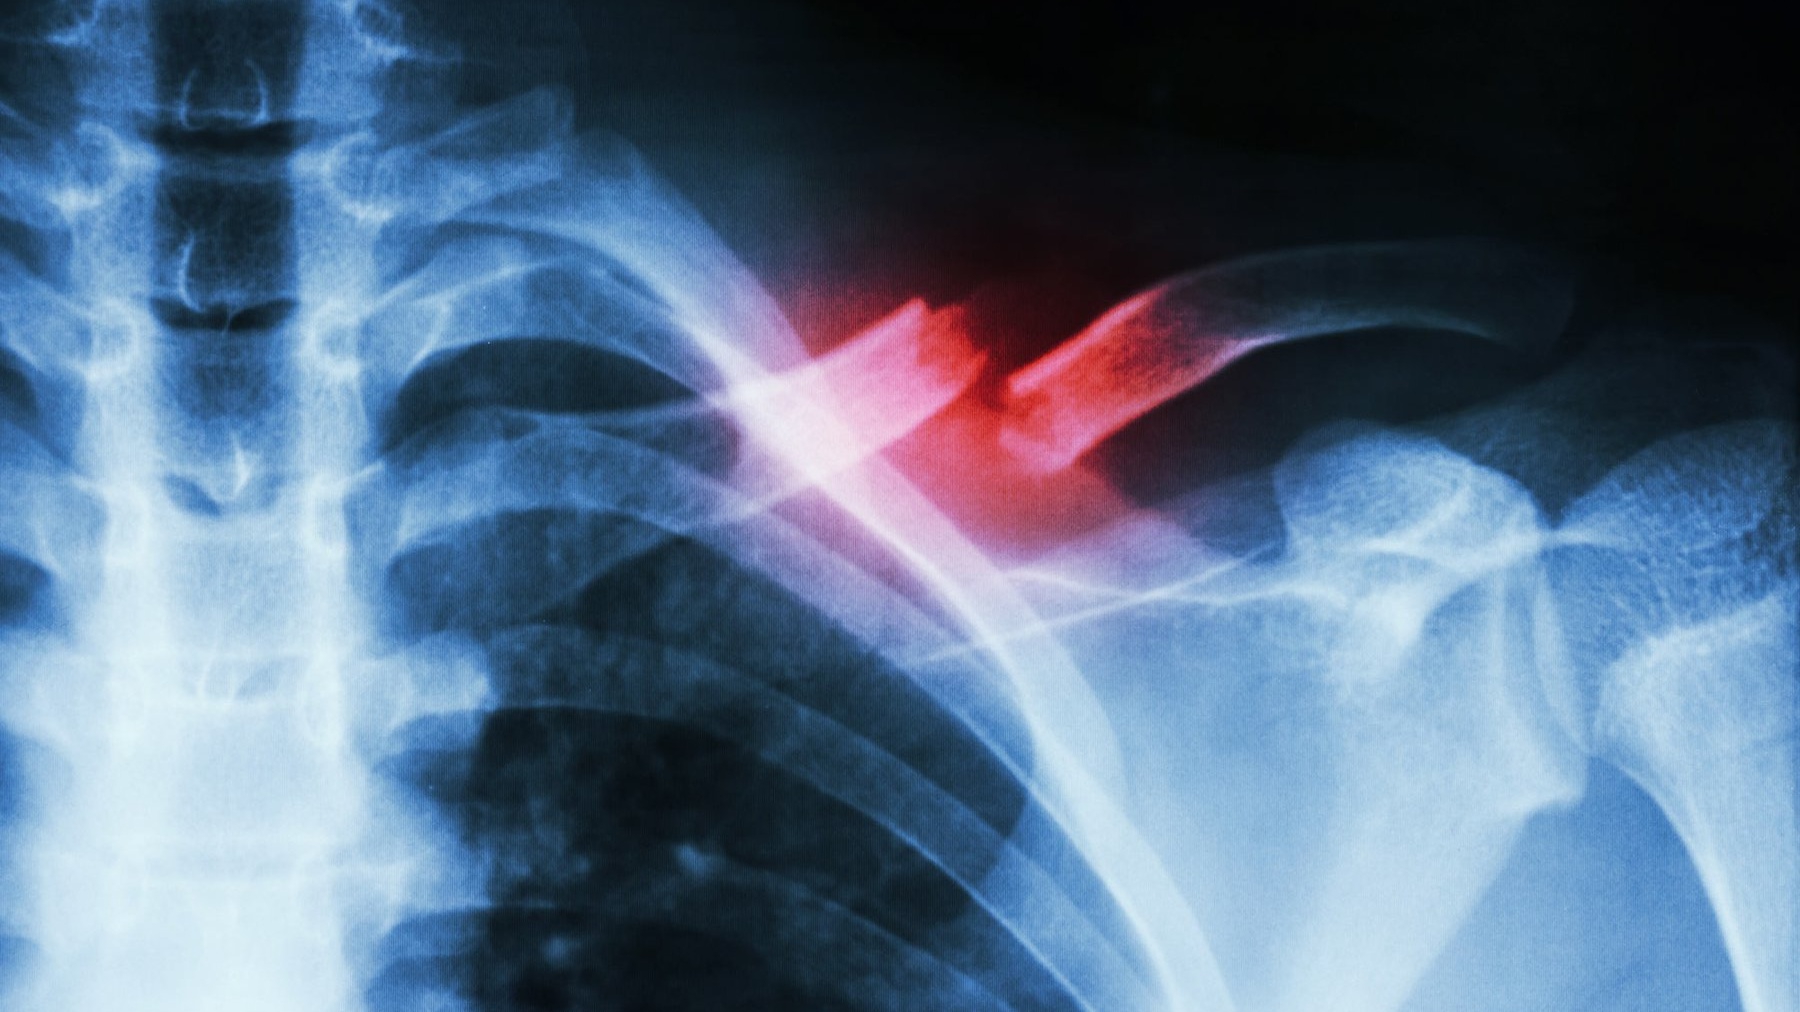

Gãy xương ức

Gãy xương ức là dạng chấn thương mạnh ảnh hưởng trực tiếp đến vùng ngực và bụng và khá hiếm gặp. Những tình huống va đập mạnh như: tai nạn giao thông, chấn thương khi chơi thể thao khiến vùng ngực bị va đập mạnh sẽ gây ra gãy xương ức. Lúc này, tùy lực tác động có thể gây ra vỡ và tách rời ra hoặc nứt xương ức.Thông thường, phần giữa của xương sẽ rất khó bị chấn thương và gãy. Đa số các trường hợp đều chỉ gãy ở phần góc ngoài và nơi tiếp giáp với xương sườn. Mũi xương ức bị gãy gây ra những vấn đề rất nghiêm trọng như: dập phổi, xuất huyết, bầm tím mô phổi, tổn thương tim.

Đây là chấn thương nặng nên bệnh nhân cần đến bệnh viện khám và điều trị ngay. Nếu không sơ cứu và có biện pháp chữa trị kịp thời, bệnh nhân có thể gặp phải những biến chứng nguy hiểm.